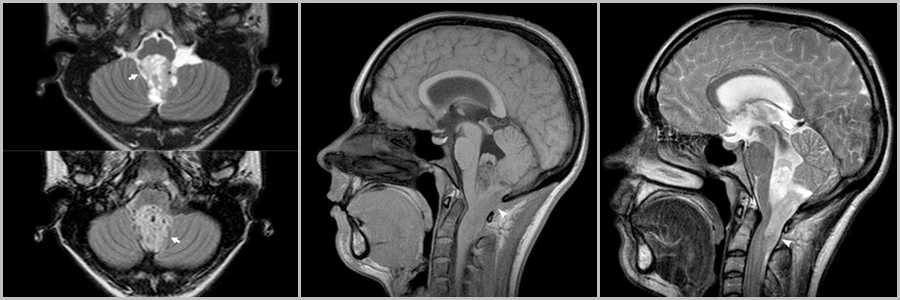

Локализация

Киста с узлом более характерна для инфратенториальной локализации опухоли, а солидное образование для супратенториальной.

Рис.4

Опухолевая киста в гемисфере мозжечка (звёздочки на рис.4 и головка стрелки на рис.4), приводящая к сужению IV желудочка и вызывающая окклюзионную гидроцефалию с расширением желудочковой системы (головки стрелок на рис.4).

При локализации в задней черепной ямке (60%) опухоль может происходить в любом месте мозжечка – из полушария или червя .

Рис.5

Пилоцитарная астроцитома растет вдоль зрительных трактов (головки стрелок рис.5), а так же неравномерно контрастируется (головки стрелок на рис.5).

Рис.6

Супратенториально локализуется в области дна III желудочка (часто ассоциированы с НФ1) и хиазмы (25 — 30%).

Кистозно-солидное образование в области III желудочка (головки стрелок на рис.6). Следы оперативного лечения в виде повреждения ствола мозолистого тела (стрелка на рис.6). Опухоль полностью не удалена (стрелка на рис.6), неоднородный конгломерат гетерогенно накапливает контраст (головка стрелки на рис.6).

Другие, менее распространенные места: мозговой ствол, полушария головного мозга и желудочки мозга (чаще у взрослых).